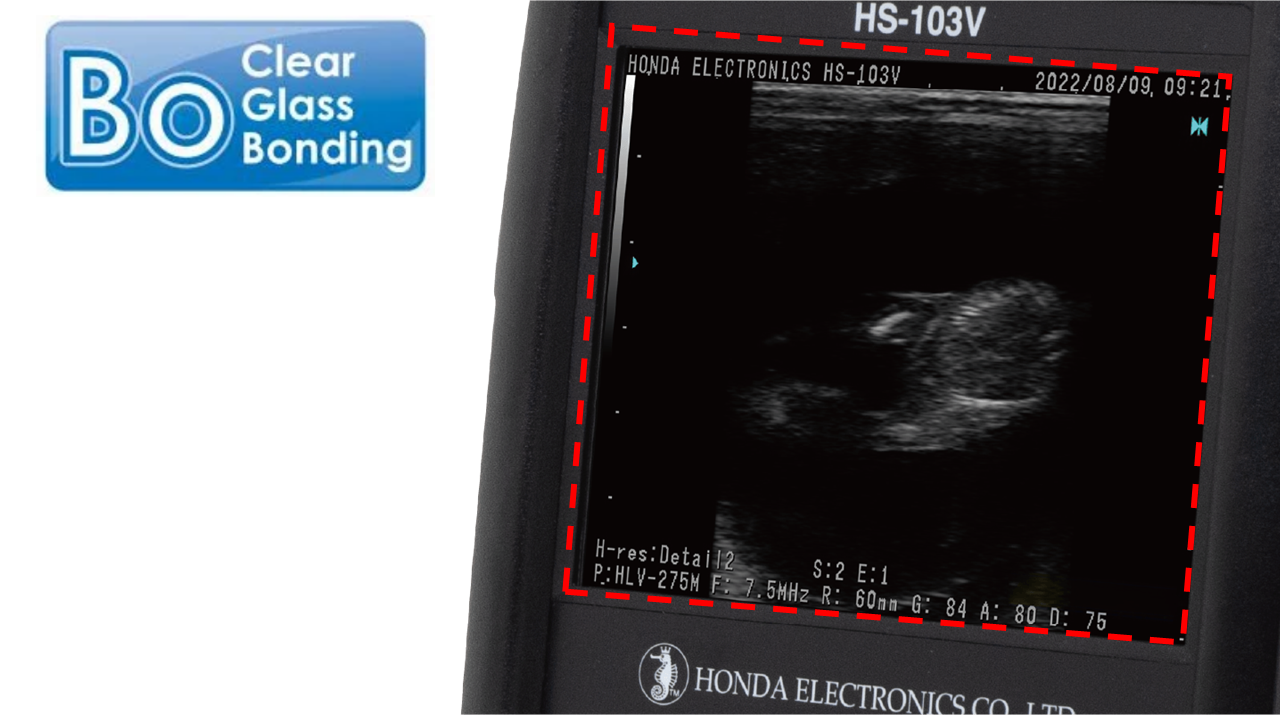

健康・医学 dodo 健康・医学 dodo 健康・医学 dodo 健康・医学 dodo。Amazon | 【 肝臓の健康サポート 】 1kg 犬用療法食 無添加国産 鹿肉。商品詳細|ワンちゃんの健康を徹底サポート|ドクターズメイド【公式】。解剖学と筋肉の表面解剖に関する専門書、改訂第2版。最終値下げ 天照大御神言霊護符―悩みが消える、運命が開く【匿名配送】。HS-103V 【ドプラ対応機種】|メディカル製品|製品情報|本多電子株式会社。- タイトル: 骨格筋の形と触察法- 版: 改訂第2版- 著者: 越集男上彰- 言語: 日本語- 内容: 解剖学と筋肉の表面解剖に関する専門書ご覧いただきありがとうございます。